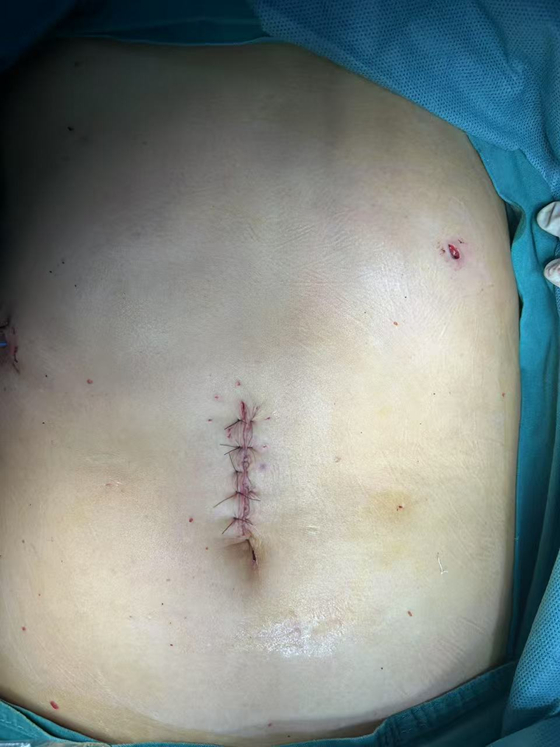

近日,湘雅常德医院普外科成功为一名61岁男性患者实施高难度腹部去分化脂肪肉瘤切除手术。本次手术的成功实施,充分体现了湘雅常德医院在复杂肿瘤诊治方面的综合实力。  ...